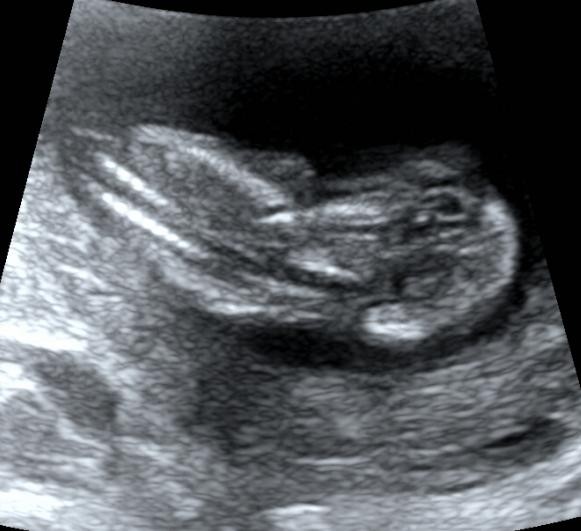

当然,这个时期我们除了重点观察TA的肢体以外,此时需要重点关注NT。

NT测量一般在11-13+6周内进行。

此时测量彩具有参考意义,但测量NT完全看宝宝的心情。

因为TA 有时候真的很不给面子。。。

比如:

有这样趴着的;

还有倒立的

还有直接给个背影的。。。。